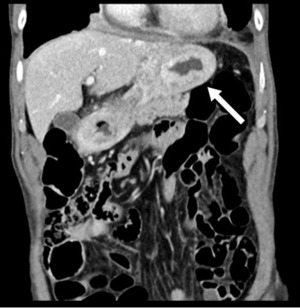

An 80-year-old previously healthy man presented to a tertiary hospital with two weeks of dyspnea, along with progressive solid food dysphagia and weight loss over one month. He had no significant medical history, family history, or psychosocial factors relevant to his current presentation. The primary concern was a rapidly worsening inability to swallow solid foods, associated with profound fatigue and a marked decrease in appetite. A computed tomography (CT) scan revealed extensive circumferential mural thickening involving a long segment of the esophagus, as well as the entire stomach and duodenum, accompanied by regional lymphadenopathy and bilateral pleural effusion (Figure 1).